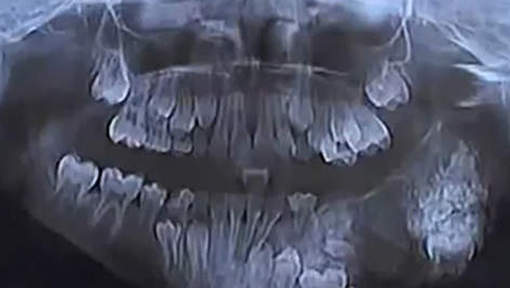

Il y a quelques jours, un petit indien de 7 ans s'est fait retirer pas moins de 80 dents au cours d'une opération.

Au départ, le jeune patient s'était rendu à l'hôpital suite à un abcès à la mâchoire supérieure. Mais après des examens plus poussés, les résultats ont révélé que l'enfant souffrait d'une tumeur bénigne. Les médecins l'ont donc opéré pendant près de 4 heures, avant de lui retirer 80 dents !

Le personnel soignant explique que s'il était venu les voir dans quatre ans, il aurait probablement eu plus de 200 dents.